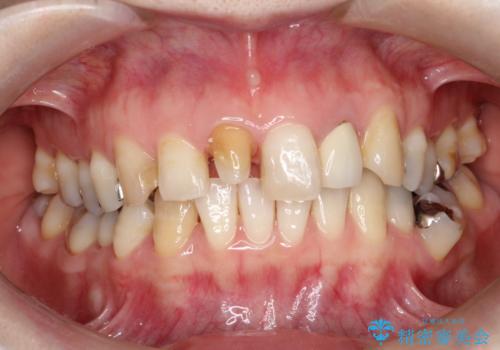

- 他院で装着された保険の前歯のかぶせ物が、他と歯と馴染まないので、自然な歯にしたいとのことで来院されました。

右上の1番目の歯の保険のかぶせ物と金属の土台を、ファイバーコアとオールセラミックにて再補綴する計画としました。

形態も色調もまわりの歯とは、調和がとれておらず、目立っていました。